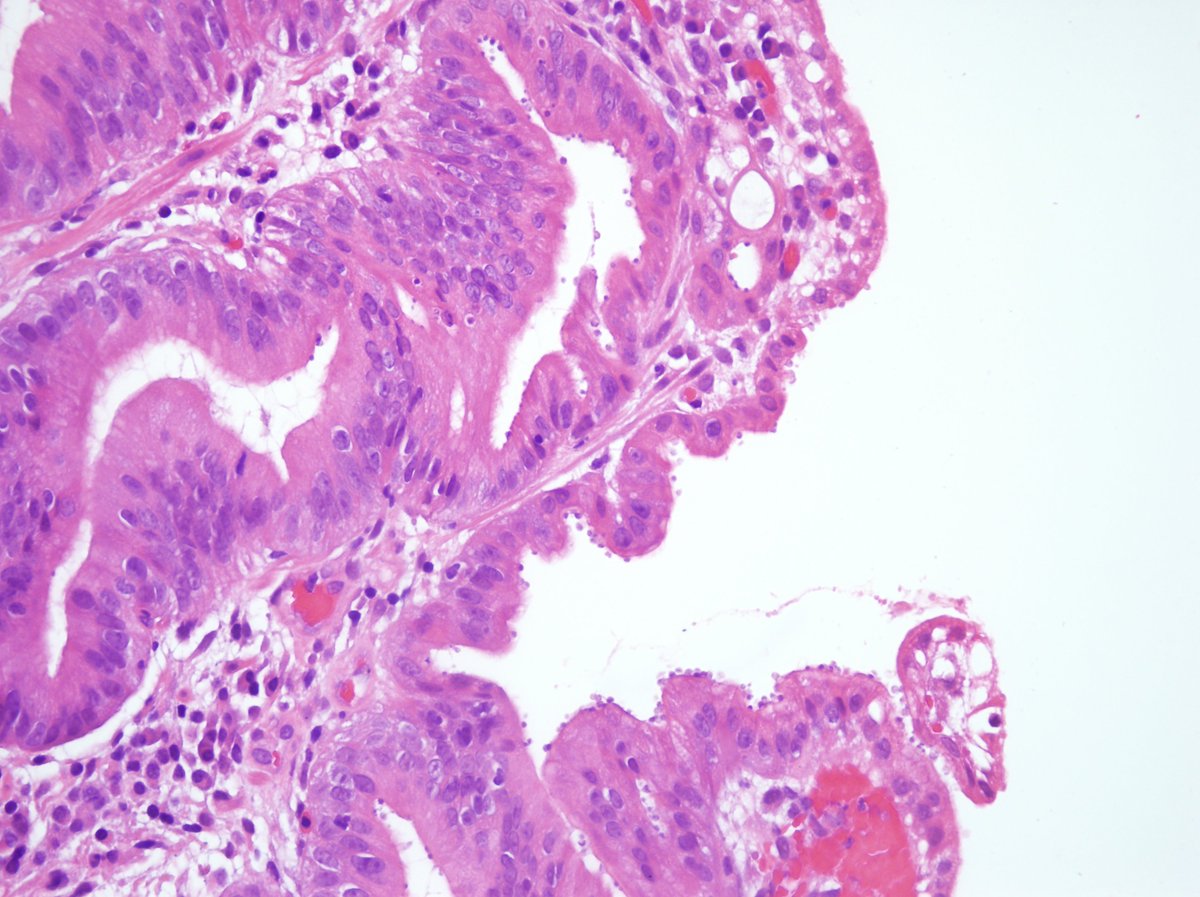

This gastric adenoma has foveolar differentiation and focal high grade dysplasia.  It is seen in pristine uninflamed mucosa. It could be argued that the lesion is atop a fundic gland polyp. This type of lesion is associated with familial adenomatous polyposis (FAP). #UMiamiPath